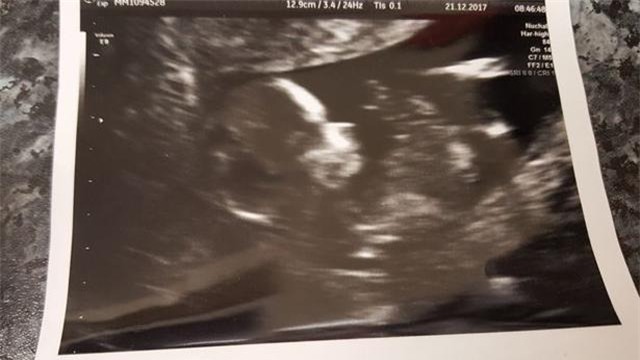

Phim chụp cho thấy thai nhi bị mắc hội chứng bất sản thận hai bên.